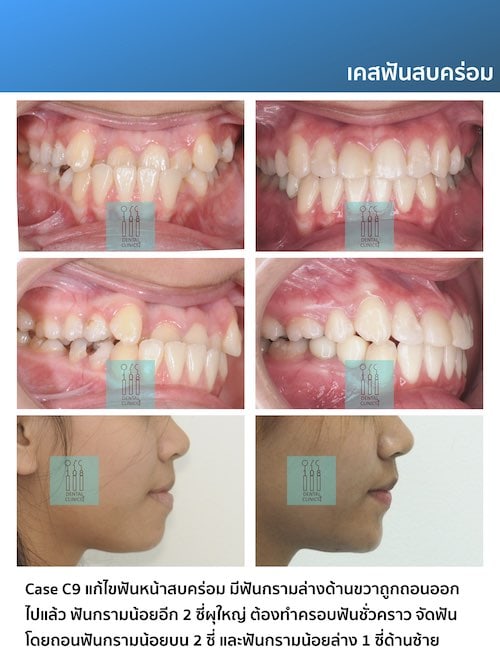

รีวิวเคสจัดฟัน

Review

ติดตามตัวอย่างผลงานเคสจัดฟันของทางคลินิกทันตกรรม 108 ได้ที่

เพื่อให้ทุกๆท่านมั่นใจในคุณภาพการรักษาของทางคลินิก เรายังมีเคสรีวิวอีกมากมายให้คนไข้ได้รับชมและพิจารณานะคะ มาขอดูเคสตัวอย่างแบบชัดๆ 4k retina ไร้ลายน้ำ กันได้ที่เคาน์เตอร์บริการของคลินิกทันตกรรม 108